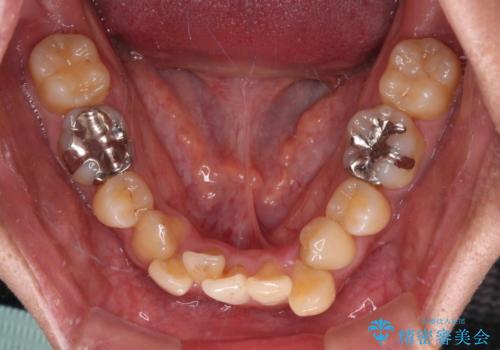

- 下顎の八重歯を気にして来院された患者様です。

左下以外、3本の第一小臼歯が既に抜去されており、左下は八重歯になっている状態でした。

左下の八重歯は手前に傾斜していたため、インビザラインによる抜歯矯正が可能と判断し、後方にある第一小臼歯を抜歯してインビザラインにて矯正治療を行うこととしました。

ワイヤー矯正と比較すると、八重歯が後方に傾斜した仕上がりとなりましたが、患者様ご希望のインビザラインにて十分な歯列を達成することができました。